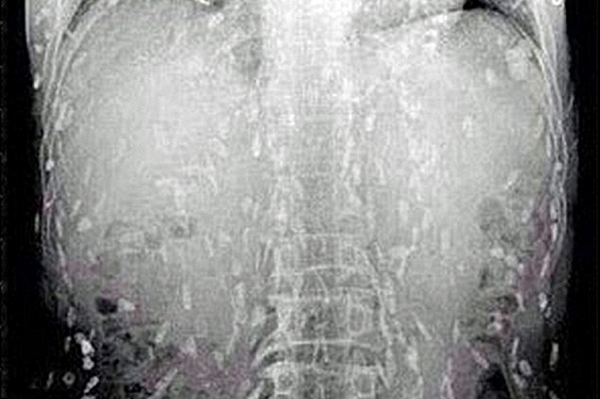

Китаец из провинции Гуандун обратился к врачу с жалобами на боли в животе и кожный зуд. Снимки, которые сделали в клинике, показали, что все его тело заражено червями-паразитами. По мнению врачей, причиной тому послужила чрезмерная любовь мужчины к сашими - блюду национальной японской кухни, которое готовится из сырой рыбы.